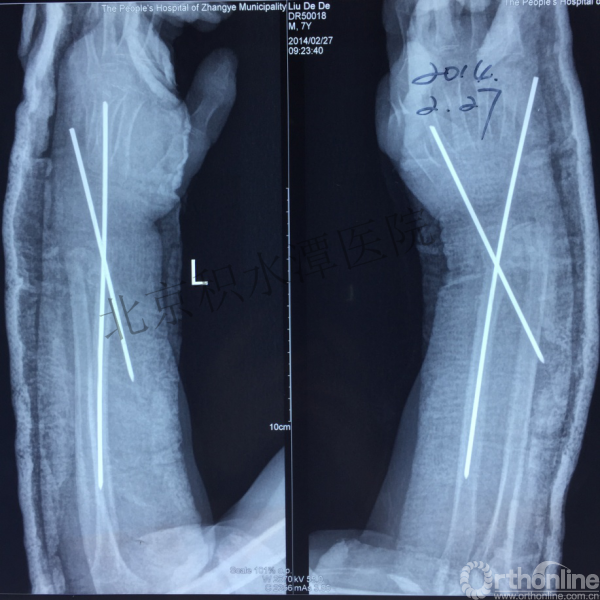

病例分享三

男孩、9岁,滑雪受伤,胫腓骨螺旋形骨折(粉碎性)

这个病例郭教授在积水潭医院骨科高研班时多次讲到,也在互动交流中惊人地看到,了解到现实之令人难以想象!

手法整复,石膏制动!

整复后7天

儿童具备强大的愈合潜力,同样也有极强的塑形能力